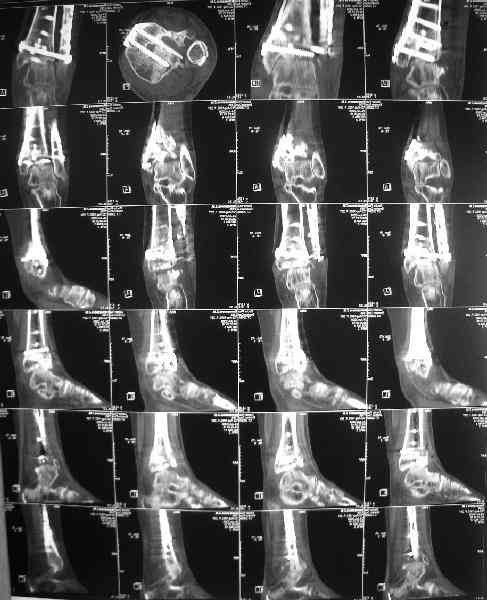

Последствия перелома пилона

Dear коллеги, Обратилась женщина, 25 л. 8 мес. назад в одной из больниц сделан остеосинтез пилона. На сегодня ходит без дополнительной опоры, хромая на поврежденную ногу. Движения в голеностопном суставе еще есть. Снимки в приложении.

Вопрос - что делать? Замыкать сустав пациентка пока не настроена (наверно, получится настроить, если задаться такой целью). Нет ли смысла попытаться сделать какую-то восстановительную операцию? Допустим, получится устранить подвывих, восстановить межберцовые соотношения - это что-то хорошее надолго даст? Или упросто убрать "железо", и этим ограничиться, пока сама не придет за артродезом?

Есть ли здесь смысл пытаться организовать эндопротезирование? В смысле, доступные сейчас протезы применимы в этой ситуации?

A female, 25, 8 month ago operated elsewhere. To date walks without support with pain and limp. The ankle is mobile yet. Images attached. The question is what to do now? The patient is not very keen on ankle fusion (though likely could change her mind if necessary) Is it worth to try a reconstruction procedure and what kind? Maybe it allows to restore alignment and tibio-fibular relationship - will it provide painless limb for more or less significant time? Or just remove the hardware and leave her alone until she herself comes for fusion?

Are available total ankle implants suitable for the situation? If yes what one?